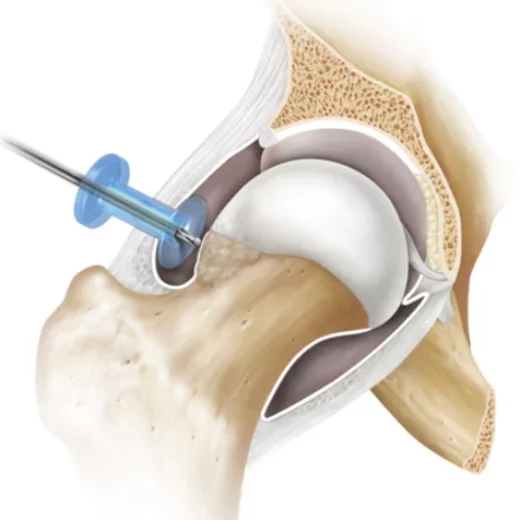

Information médicale complète à destination des patients Cette page a pour objectif de fournir une information claire, détaillée et approfondie sur le conflit fémoro-acétabulaire (CFA), également appelé femoroacetabular impingement (FAI). Elle s’adresse aux patients souffrant de douleurs de hanche, en particulier aux adultes jeunes et physiquement actifs, et vise à répondre aux questions les plus fréquentes concernant le diagnostic, les...